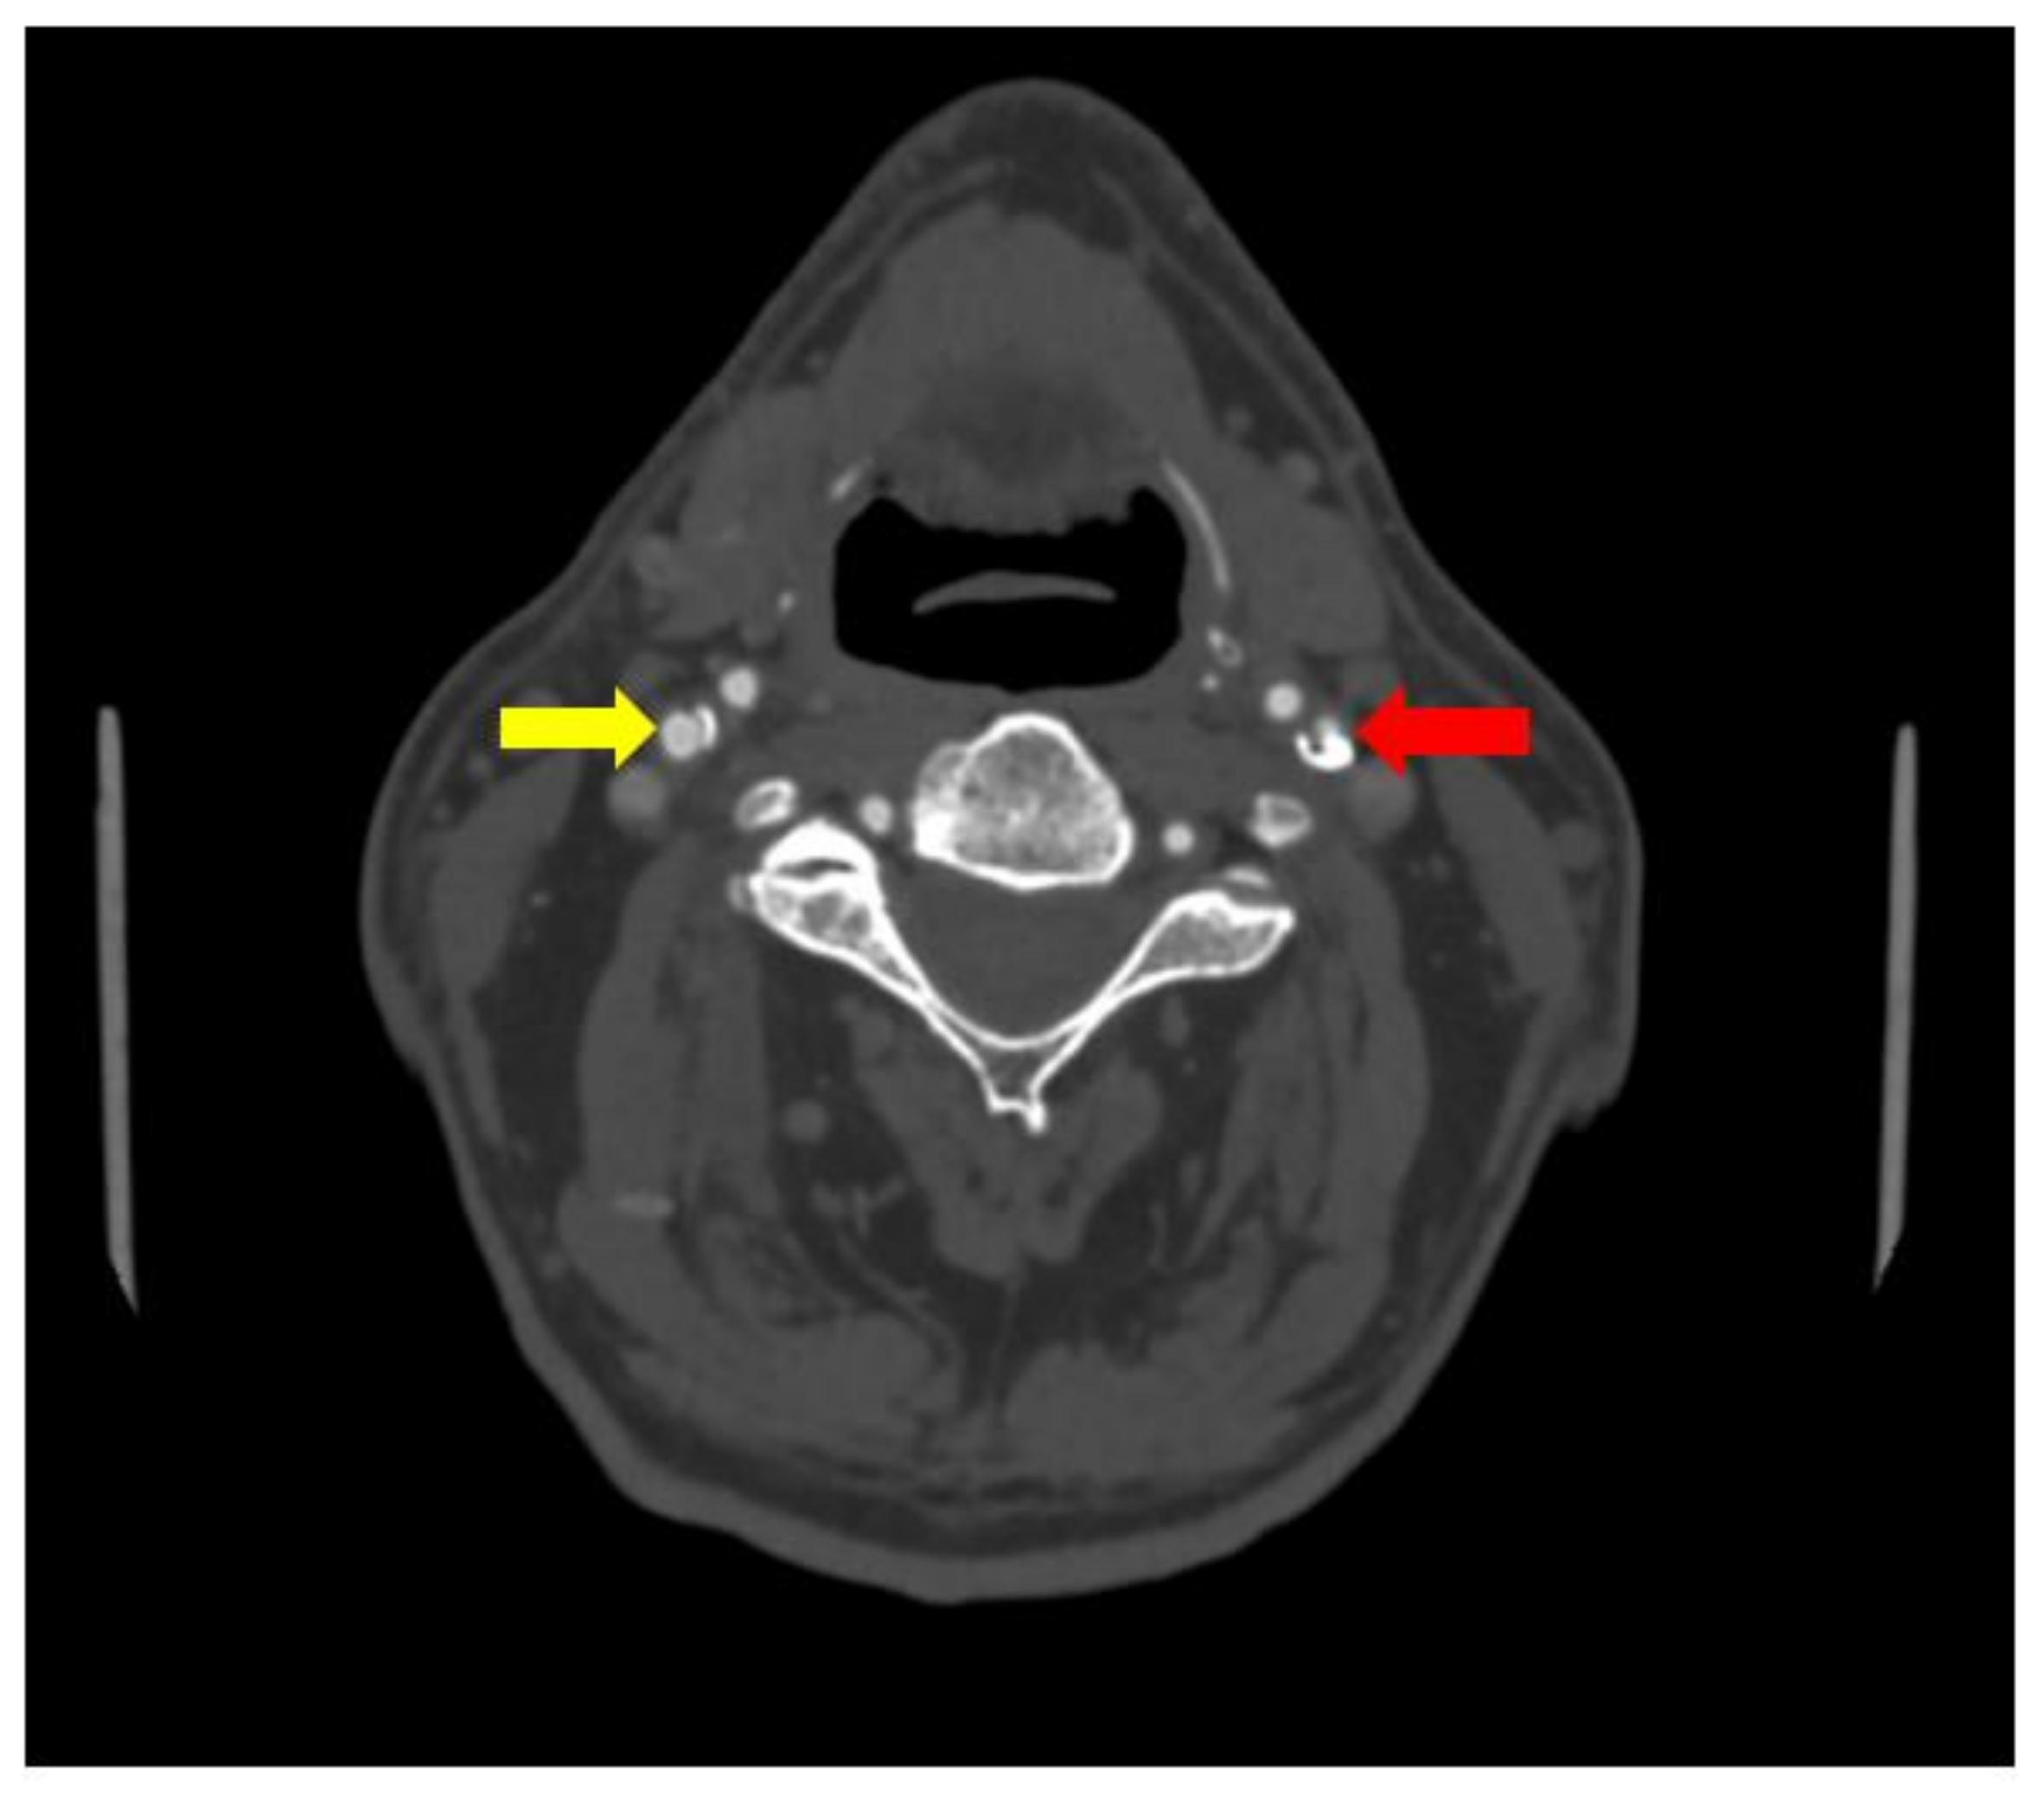

No significant changes were noted in the patient blood tests and patient urine analysis. When performed computed tomography angiography (CTA), subocclusion in the proximal segment of the left internal carotid artery was seen, as well as 30% stenosis in the proximal segment of the right internal carotid artery was observed (see Figure 1 and Figure 2).

Figure 2. Subocclusion in the proximal segment of the left internal carotid artery (red array) and 30% stenosis in the proximal segment of the right internal carotid artery (CTA) (yellow array).